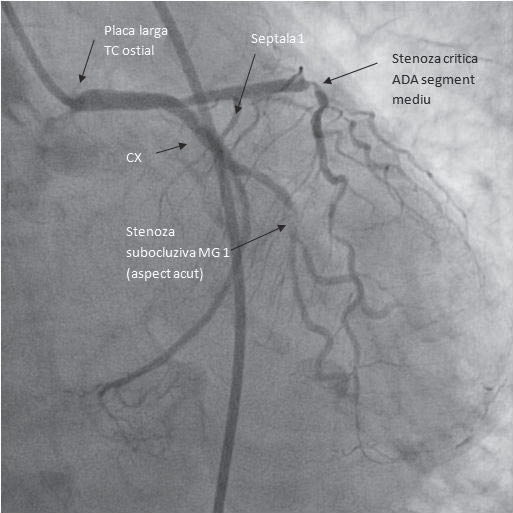

Clinical examination on admission: mediocre general condition, conscious, cooperative, BP-150/76 mmHg, HR (heart rate)=75/min, grade III/VI systolic murmur in the mitral focus irradiating in the armpit, subcrepitant pulmonary rales in the basal 2/3, 82% oxygen saturation corrected with O2 on the mask with 10 l/min to 86%, turgescent jugular veins. Echocardiography on admission: EF=40%, akinesia of inferior wall and 2/3 apical lateral wall, severe mitral regurgitation, severe tricuspid regurgitation, severe pulmonary hypertension, bilateral pleural fluid. Coronary angiography reveals subocclusion of the circumflex artery and 80-90% stenosis of anterior descending artery in the first segment (Figures 19 and 20). Primary balloon angioplasty is performed in the circumflex artery (small caliber vessel) (Figure 21) and it is decided to perform stent angioplasty of the lesion on the anterior descending artery (Figure 22) due to the patient’s hemodynamic instability, with a good final result. Immediate revascularization of the significant lesions that are not incriminate in causing STEMI during the same procedure with primary angioplasty of the incriminated vessel may be considered in some patients (class of indication IIb recommendation level B) according to the ESC/EACTS Guidelines on myocardial revascularization – 2014 5.

Figure 19. Caudal incidence (34°). Left main with a plaque at the origin. CXA with a subocclusive stenosis at the marginal I. Critical stenosis at the medium segment of ADA.

Figure 20. LAO (25°) cranial (35°). Left main with a plaque at the origin. ADA with a 30% plaque after its origin and a 90% stenosis in the middle segment.